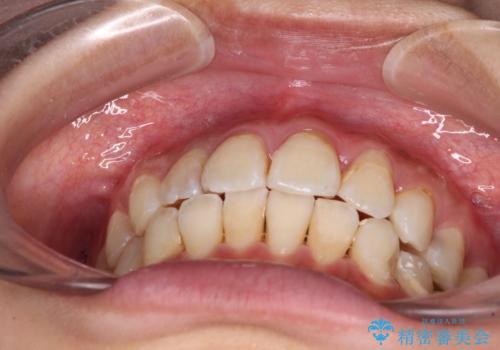

- 虫歯が多く、磨きにくい歯並びを改善したいとのことで来院された患者様です。

歯列は叢生が認められる程度でしたが、やや前突感があったので、少しでも口が閉じやすくなるように仕上げる方針としました。

神経を取り除かれている歯3本以外にも虫歯が認められたため、事前に処置を行い、インビザラインにて矯正治療を行うこととしました。

神経が取り除かれている歯は、クラウンによる補綴治療が必要であるため、矯正治療後にオールセラミッククラウンにて補綴治療を行うこととしました。